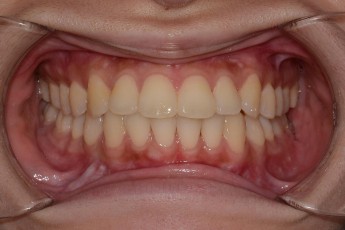

BEFORE & AFTER